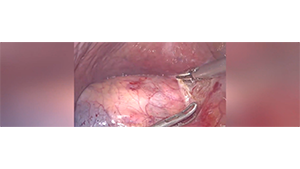

腹腔镜下左半肝切除术

作者:孙吉春 | 作者单位:中南大学湘雅三医院